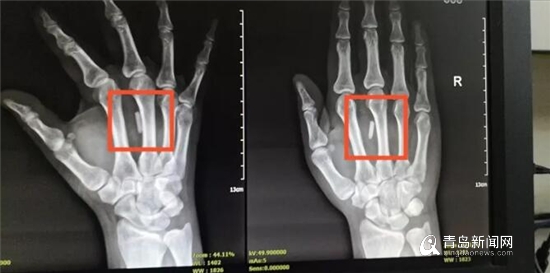

X线片显示男子右手掌心有异物。

为尽快缓解患者的痛苦,医生连夜安排检查,x线片提示右手掌心有异物!为避免进一步造成伤害和感染,医生决定马上手术!

很快,医生取出了患者右手掌心中约2cm的异物——那段折断的筷子。用双氧水、碘伏水冲洗创面,并修复屈指肌腱后,一期缝合切口。手术顺利,术后患者返回病房休养,无感染迹象,身体情况正常,但此时的他懊悔不已!

医生从男子手掌中取出折断的筷子,约2cm长。